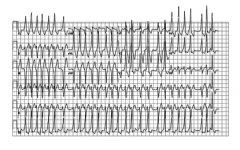

- Мултифокална предсърдна тахикардия – представлява тахикардия със сърдечна честота около 100-130 уд/мин. Характеризира се с различна морфология на Р вълните и различни Р – Р интервали. Тази тахикардия е характерна за възрастни пациенти с ХОББ, застойна сърдечна недостатъчност и може да прогресира до предсърдно мъждене. Може да се срещне и при деца. Лечението е свързано с лечението на подлежащата причина. Уместно е въздържането от бета-блокери, когато подлежащата причина е белодробно заболяване. Верапамил или амиодарон могат да бъдат използвани, а субституцията с калий и магнезий може да има ефект по отношение прекъсването на тахикардията.

Фигура.1 ЕКГ при мултифокална предсърдна тахикардия.